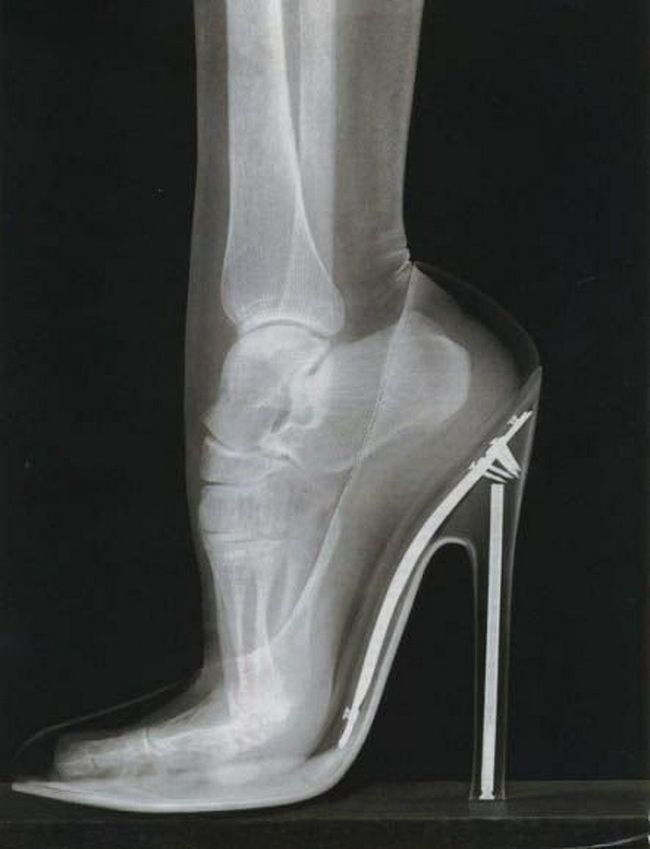

15 – Pé feminino no salto alto